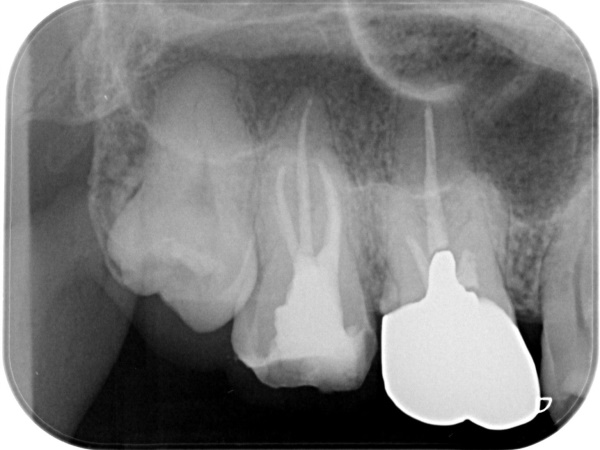

初診時